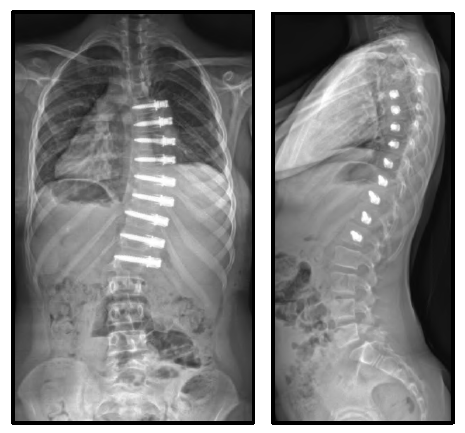

Vertebral Body Tethering

About This Treatment

Vertebral Body Tethering is a growth modulation technique that is aimed at restraining growth on one side (the convex side) of the spine while allowing growth on the other side (the concave shorter side) to continue as normal. This procedure is offered to children before their pubescent growth spurt, who have a significant scoliosis that is not responsive to any other treatment.

The aim of this guided, growth friendly intervention is that it will result in some correction of the scoliosis curvature as the spine continues to grow and therefore not require any further intervention in the future. The surgery is performed as a minimally invasive or keyhole procedure under a special anaesthetic. This procedure is not guaranteed to work and if the scoliosis continues to progress then it may require further surgery or in some cases a definitive spinal fusion at a later date.